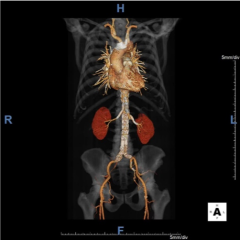

The Abdominal Imaging fellowship is based at NewYork-Presbyterian Hospital/Weill Cornell Medicine. With a large primary-care and tertiary-level referral base, the clinical service is comprised of a high-volume and full scope of abdominopelvic imaging. Fellows gain experience with cutting edge GE and Siemens technology including two PET/MRI scanners (Siemens Biograph mMR and GE Signa PET/MR); GE Advantage Workstations; and multiple software platforms including TeraRecon, Vital Vitrea, SyngoVIA, and DynaCAD. Our advanced 3D Imaging Data Evaluation and Analysis Lab (IDEAL) complements the training experience with on-demand 3D reconstructions, volumes, tumor segmentation, custom MIPS, and image fusion.

- Vascular Imaging: Aneurysm evaluation, pre- and post-endovascular repair; vascular runoffs; mesenteric vessel evaluation; pre-operative mapping for autologous breast reconstruction with perforator flaps.